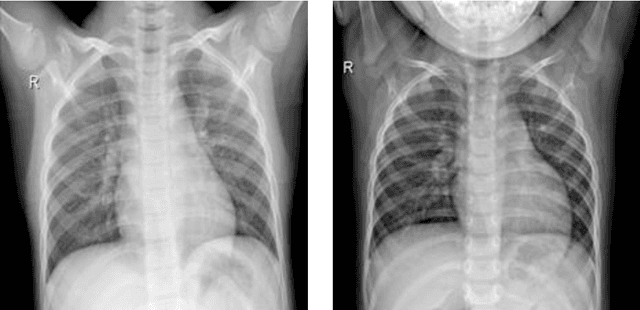

Abstract:The new coronavirus 2019, also known as COVID19, is a very serious epidemic that has killed thousands or even millions of people since December 2019. It was defined as a pandemic by the world health organization in March 2020. It is stated that this virus is usually transmitted by droplets caused by sneezing or coughing, or by touching infected surfaces. The presence of the virus is detected by real-time reverse transcriptase polymerase chain reaction (rRT-PCR) tests with the help of a swab taken from the nose or throat. In addition, X-ray and CT imaging methods are also used to support this method. Since it is known that the accuracy sensitivity in rRT-PCR test is low, auxiliary diagnostic methods have a very important place. Computer-aided diagnosis and detection systems are developed especially with the help of X-ray and CT images. Studies on the detection of COVID19 in the literature are increasing day by day. In this study, the effect of different batch size (BH=3, 10, 20, 30, 40, and 50) parameter values on their performance in detecting COVID19 and other classes was investigated using data belonging to 4 different (Viral Pneumonia, COVID19, Normal, Bacterial Pneumonia) classes. The study was carried out using a pre-trained ResNet50 convolutional neural network. According to the obtained results, they performed closely on the training and test data. However, it was observed that the steady state in the test data was delayed as the batch size value increased. The highest COVID19 detection was 95.17% for BH = 3, while the overall accuracy value was 97.97% with BH = 20. According to the findings, it can be said that the batch size value does not affect the overall performance significantly, but the increase in the batch size value delays obtaining stable results.

Abstract:Covid-19 is a very serious deadly disease that has been announced as a pandemic by the world health organization (WHO). The whole world is working with all its might to end Covid-19 pandemic, which puts countries in serious health and economic problems, as soon as possible. The most important of these is to correctly identify those who get the Covid-19. Methods and approaches to support the reverse transcription polymerase chain reaction (RT-PCR) test have begun to take place in the literature. In this study, chest X-ray images, which can be accessed easily and quickly, were used because the covid-19 attacked the respiratory systems. Classification performances with support vector machines have been obtained by using the features extracted with residual networks (ResNet-50), one of the convolutional neural network models, from these images. While Covid-19 detection is obtained with support vector machines (SVM)-quadratic with the highest sensitivity value of 96.35% with the 5-fold cross-validation method, the highest overall performance value has been detected with both SVM-quadratic and SVM-cubic above 99%. According to these high results, it is thought that this method, which has been studied, will help radiology specialists and reduce the rate of false detection.

Abstract:The 2019 novel coronavirus (COVID-19), with a starting point in China, has spread rapidly among people living in other countries, and is approaching approximately 305,275 cases worldwide according to the statistics of European Centre for Disease Prevention and Control. There are a limited number of COVID-19 test kits available in hospitals due to the increasing cases daily. Therefore, it is necessary to implement an automatic detection system as a quick alternative diagnosis option to prevent COVID-19 spreading among people. In this study, three different convolutional neural network based models (ResNet50, InceptionV3 and Inception-ResNetV2) have been proposed for the detection of coronavirus pneumonia infected patient using chest X-ray radiographs. ROC analyses and confusion matrices by these three models are given and analyzed using 5-fold cross validation. Considering the performance results obtained, it is seen that the pre-trained ResNet50 model provides the highest classification performance with 98% accuracy among other two proposed models (97% accuracy for InceptionV3 and 87% accuracy for Inception-ResNetV2).